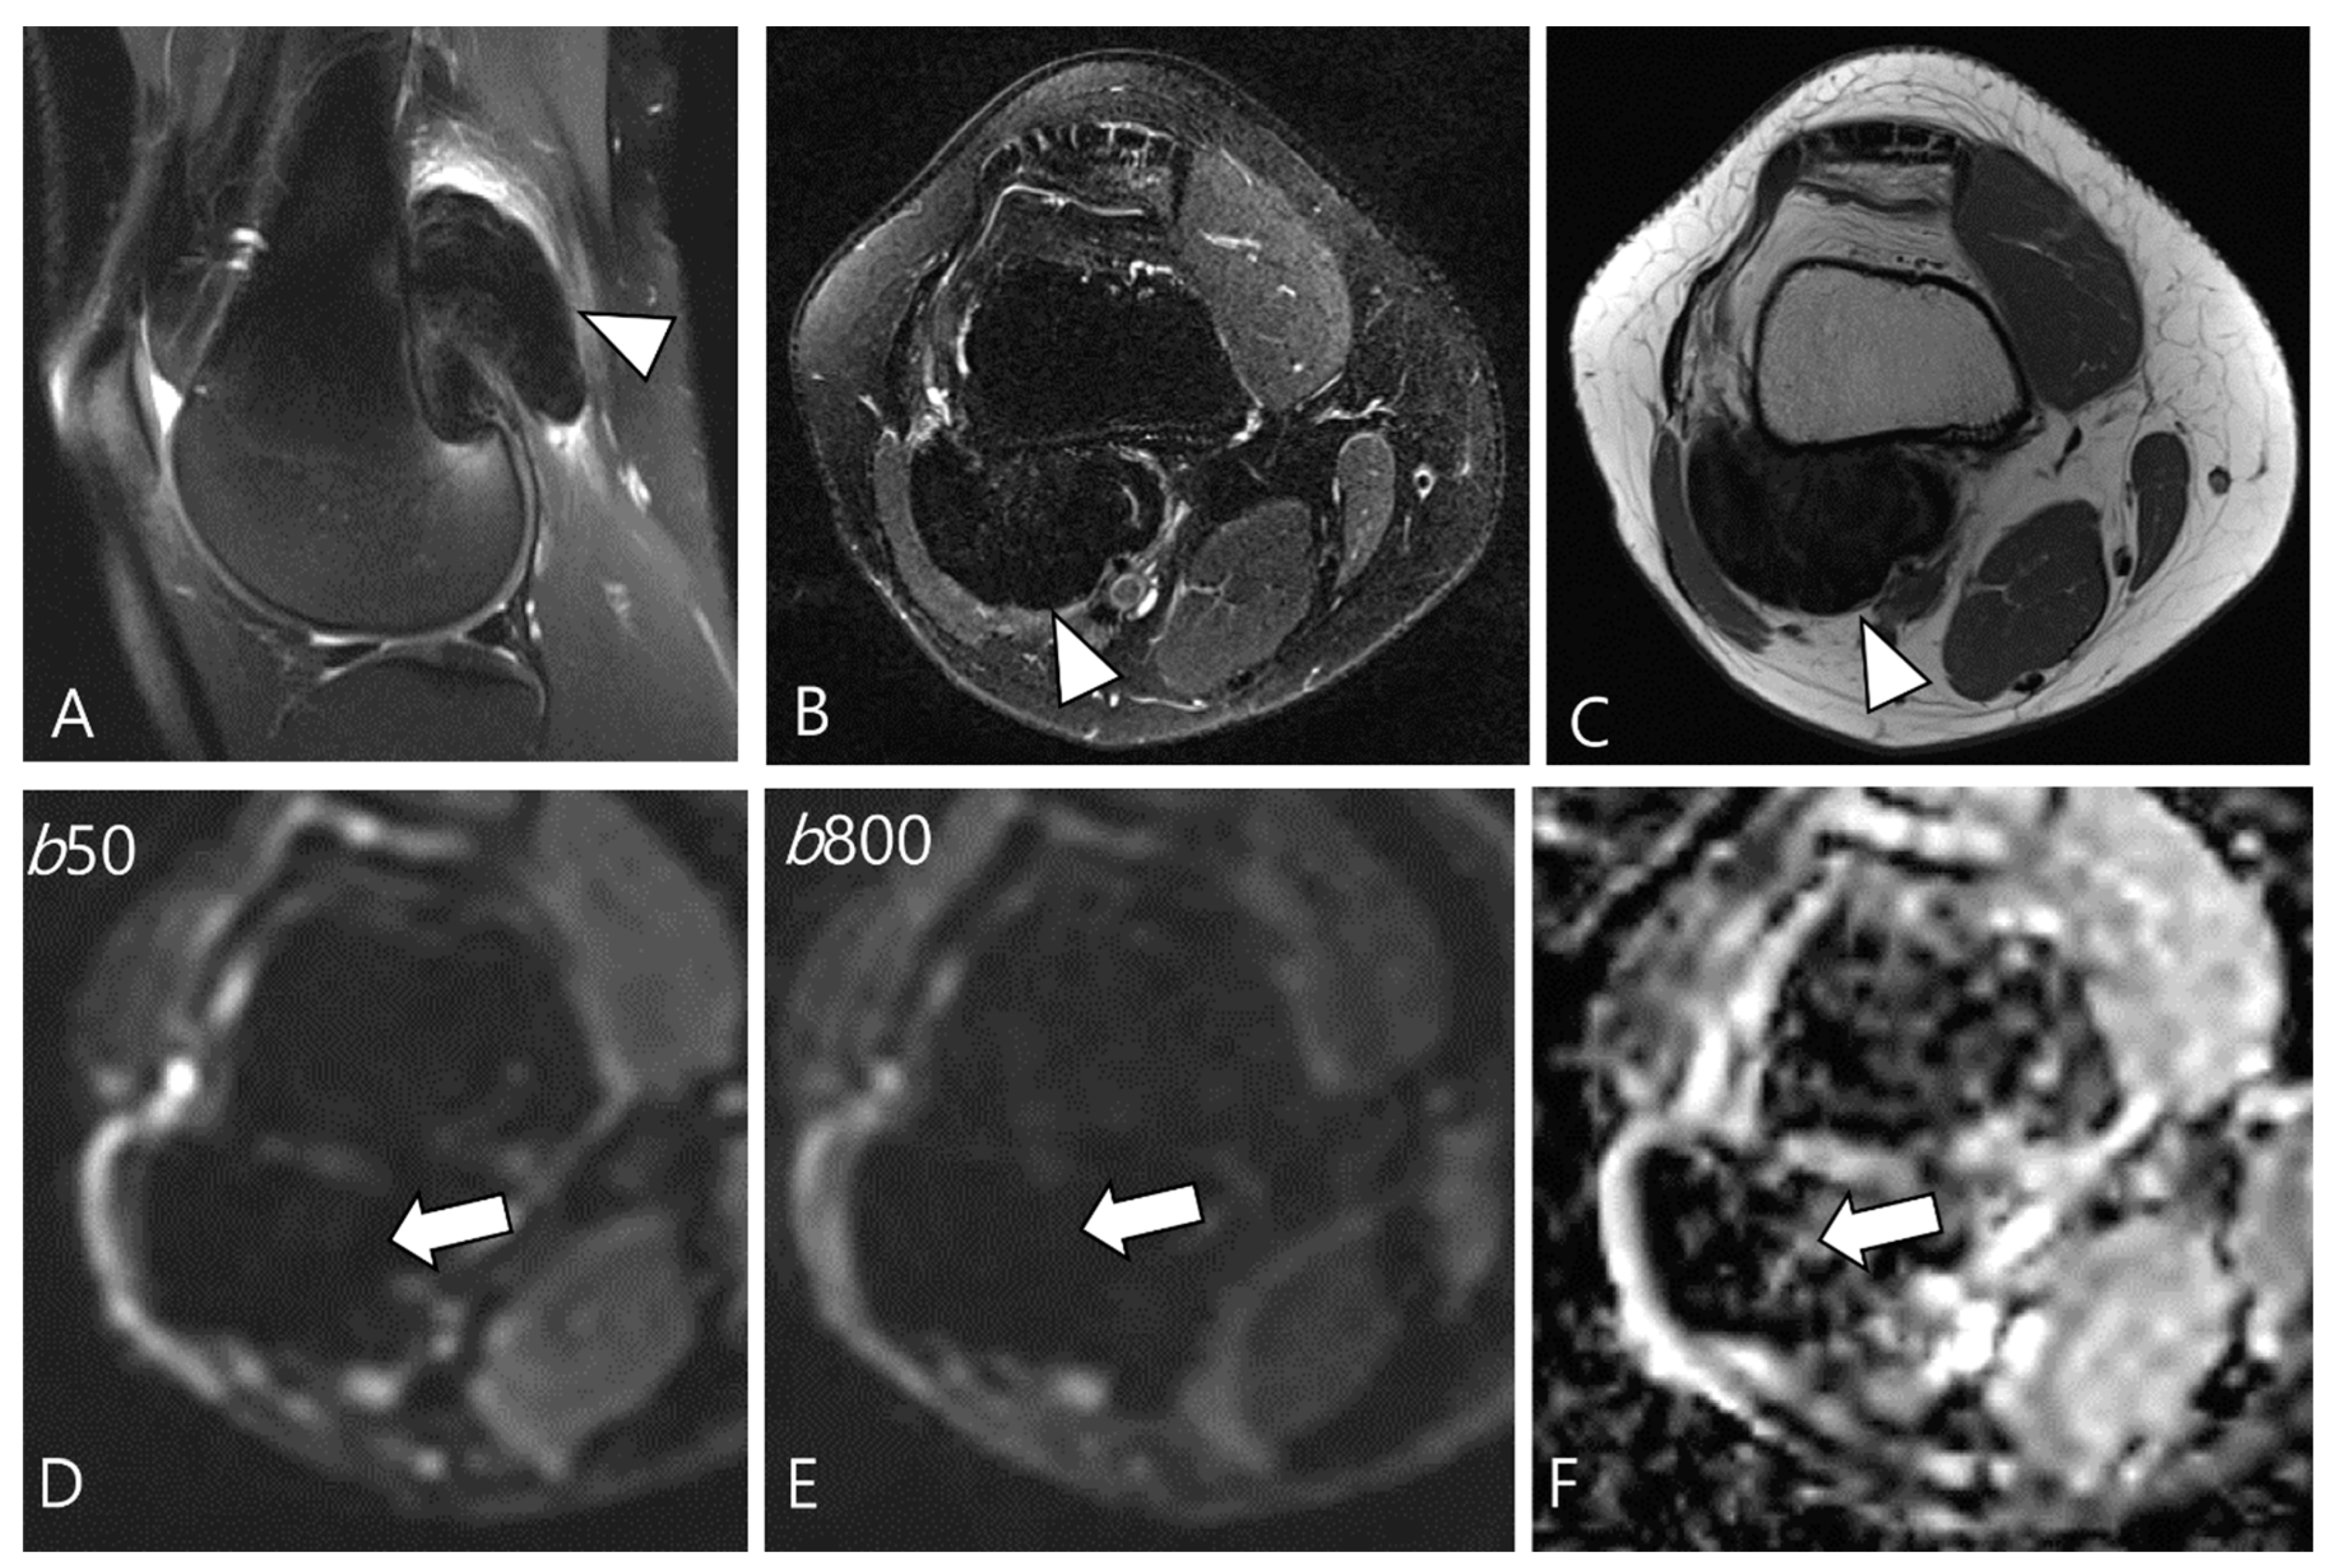

2.3. Morphological Findings for D-TSGCT

2.4. Relationship to Adjacent Structures of D-TSGCT

2.5. Advanced MRI Sequences for D-TSGCT